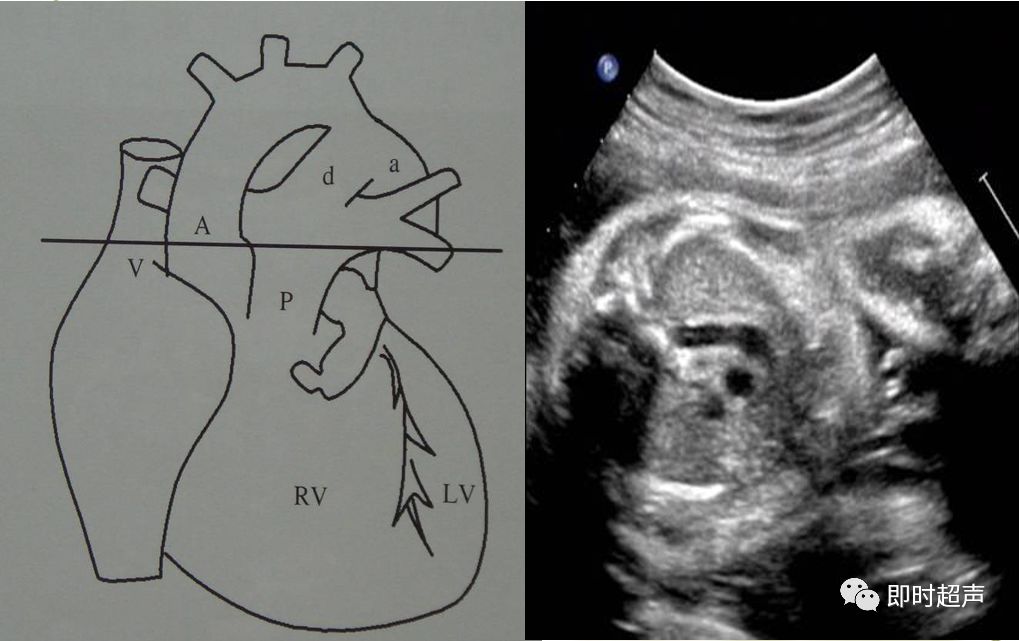

探到胎儿四腔心后,探头稍向胎儿头侧偏移即可显示三血管-气管切面,正常三血管-气管平面从左到右依次显示:肺动脉、主动脉弓、气管、上腔静脉。

胎儿正常三血管-气管平面示意图

胎儿三血管气管切面

三血管-气管切面的观察内容

- 从左到右依次是肺动脉、主动脉弓和上腔静脉

- 内径从左到右依次递减

- 主动脉弓位于气管的左侧

- 肺动脉和主动脉弓血流都流向脊柱,呈后向血流

- 肺动脉经动脉导管与主动脉弓共同汇入降主动脉